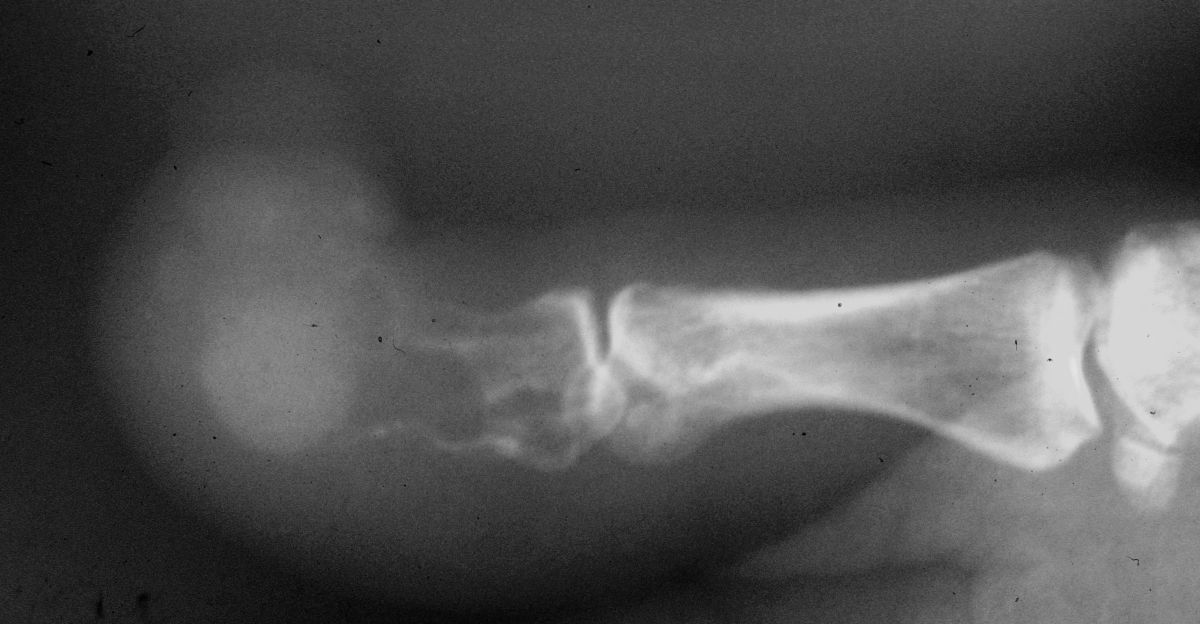

| Plain films showed

loss of the distal 2/3 of the distal phalanx. |